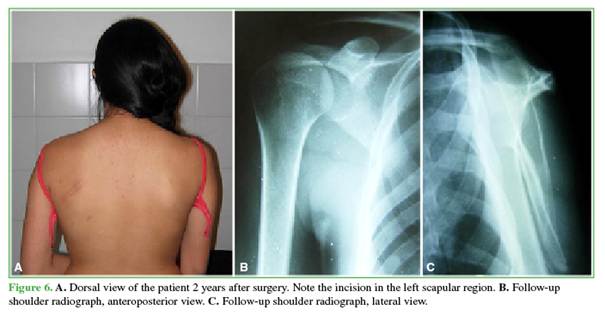

The patient progressed favorably, recovering full, asymptomatic range of motion. At 2-year clinical and radiographic follow-up, the results remained favorable (Figure 6).